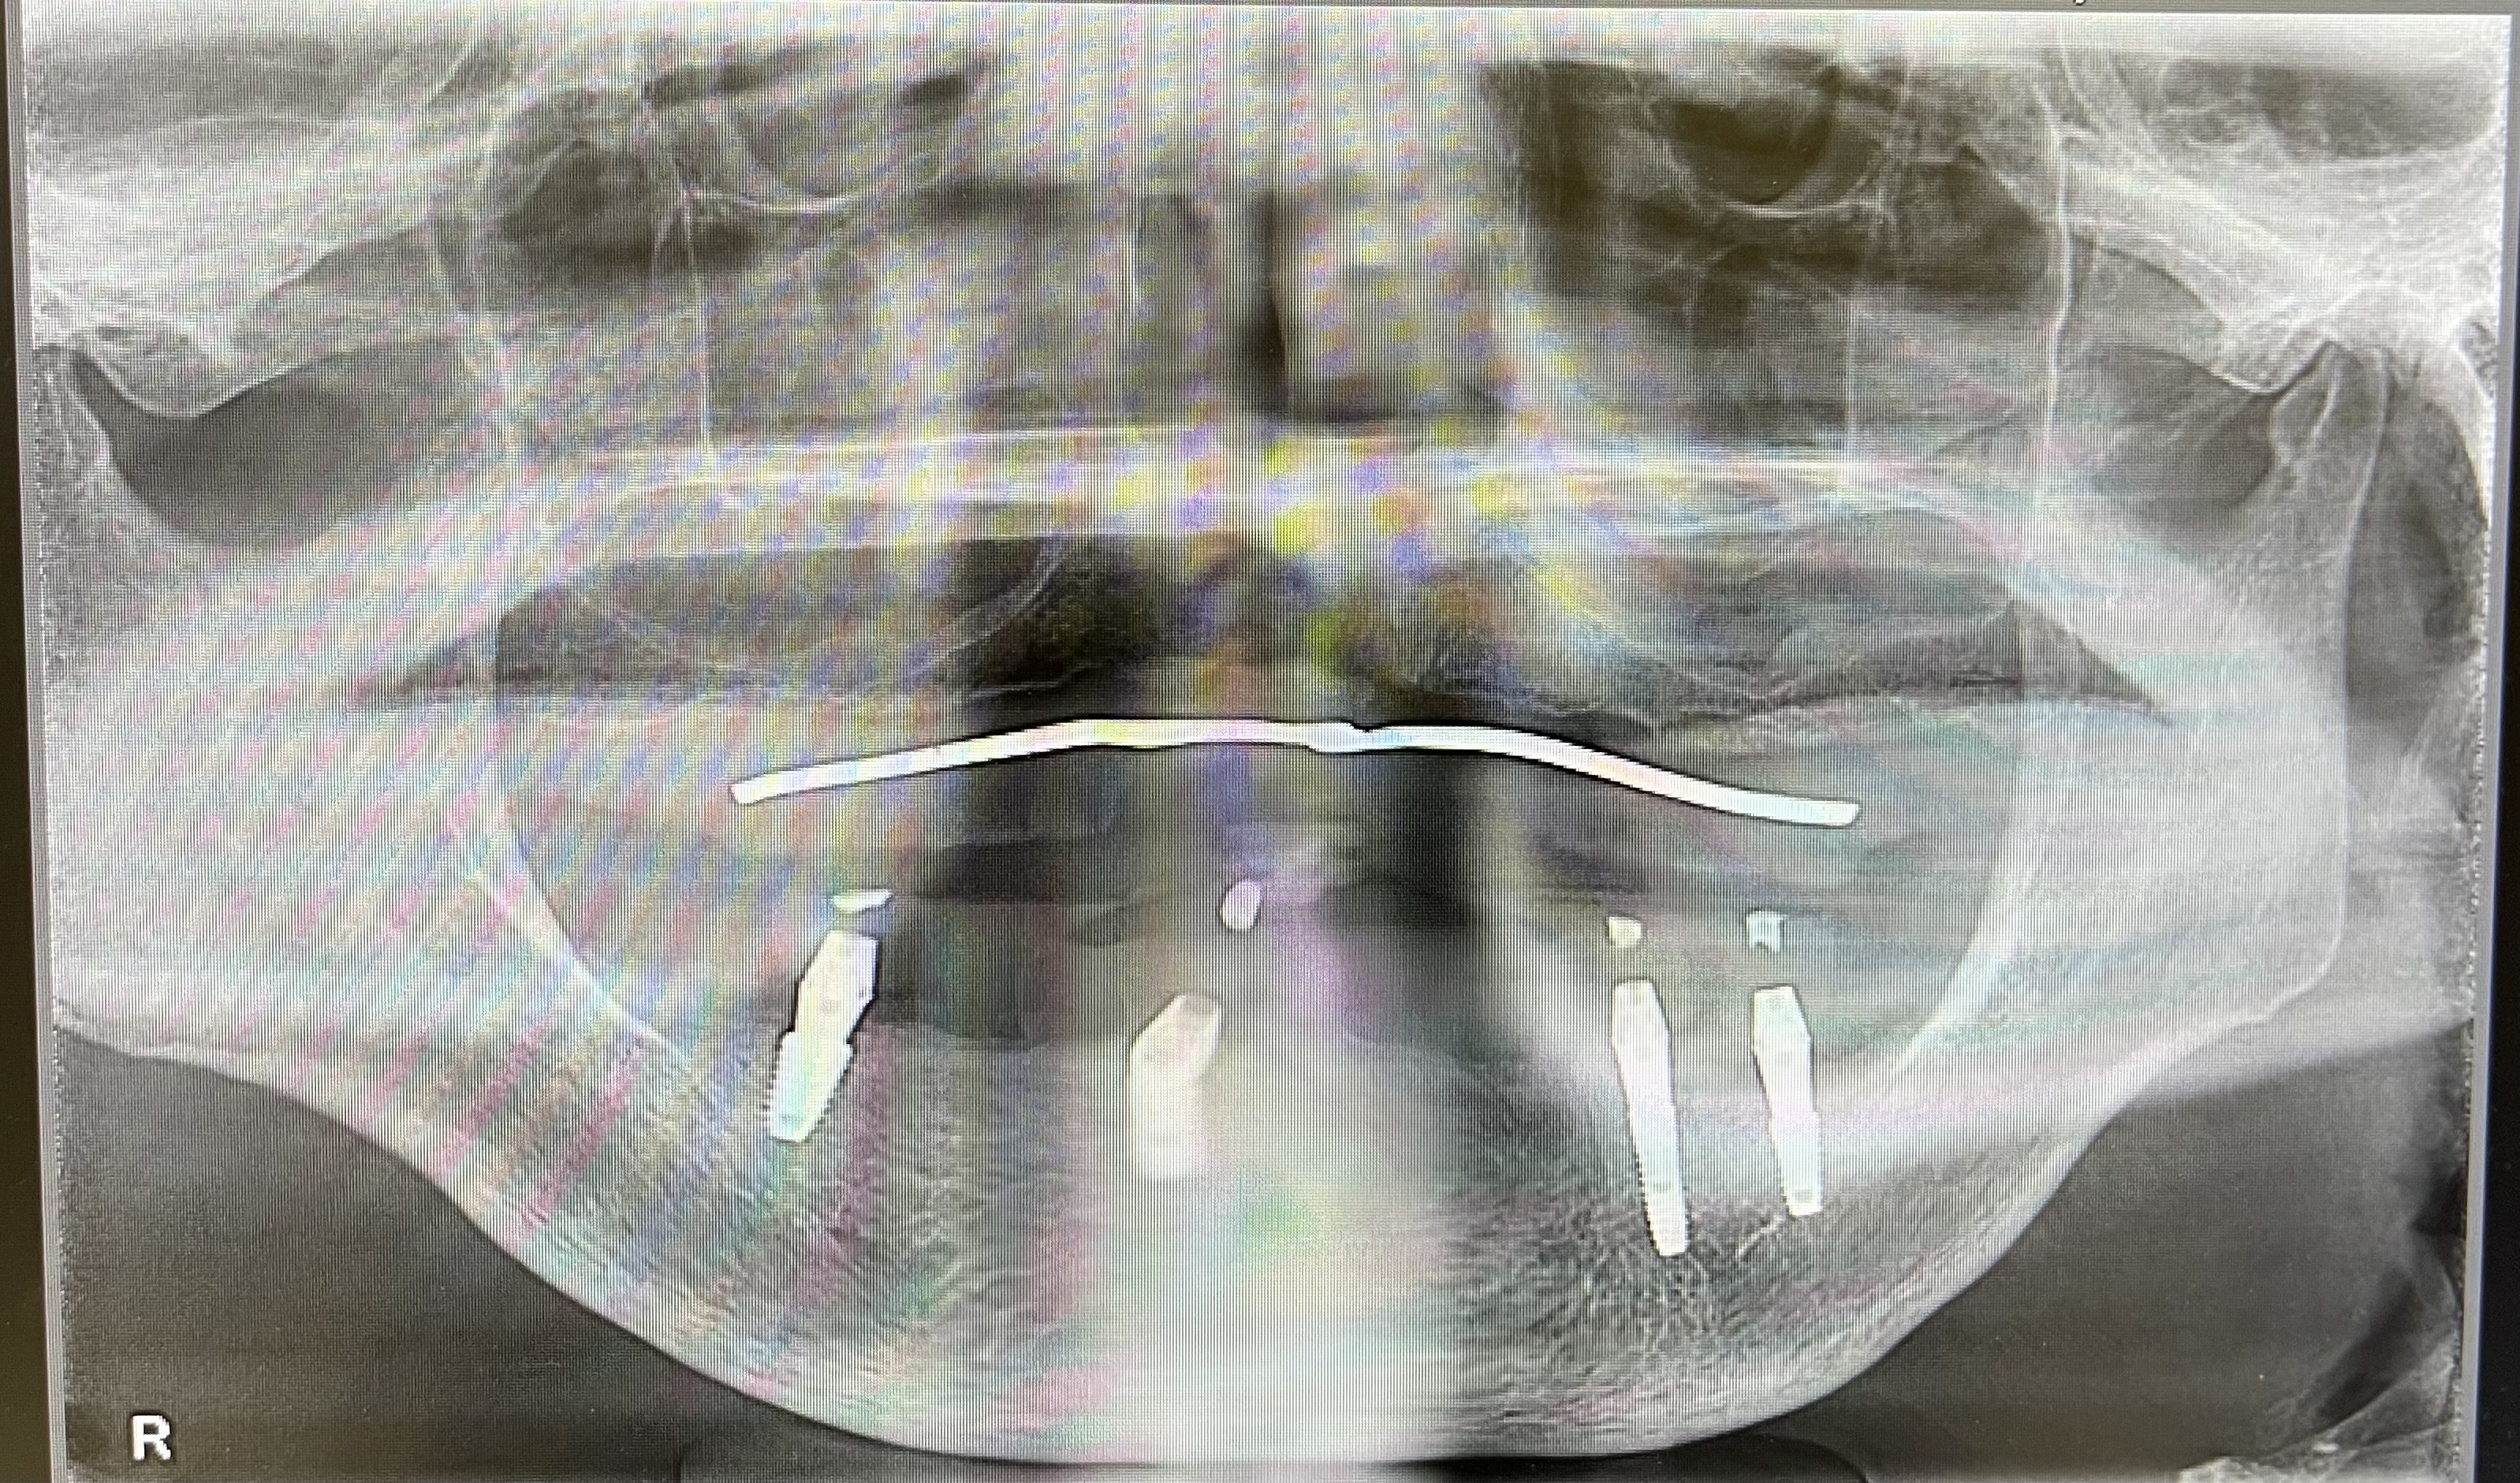

下顎インプラントを4本埋入した状態

上部構造が入っている状態(下顎パノラマ写真)